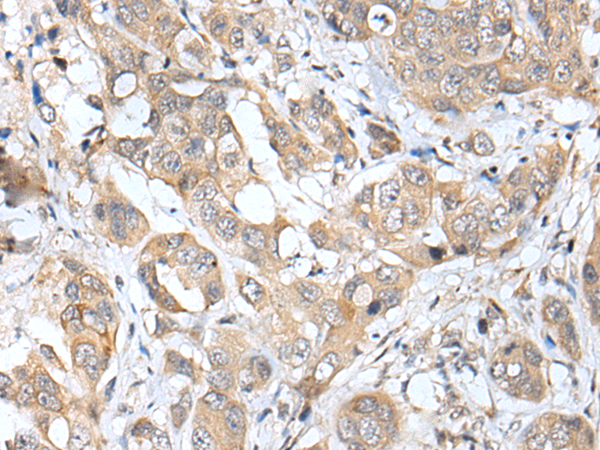

IHC positive control: |

Human breast cancer |